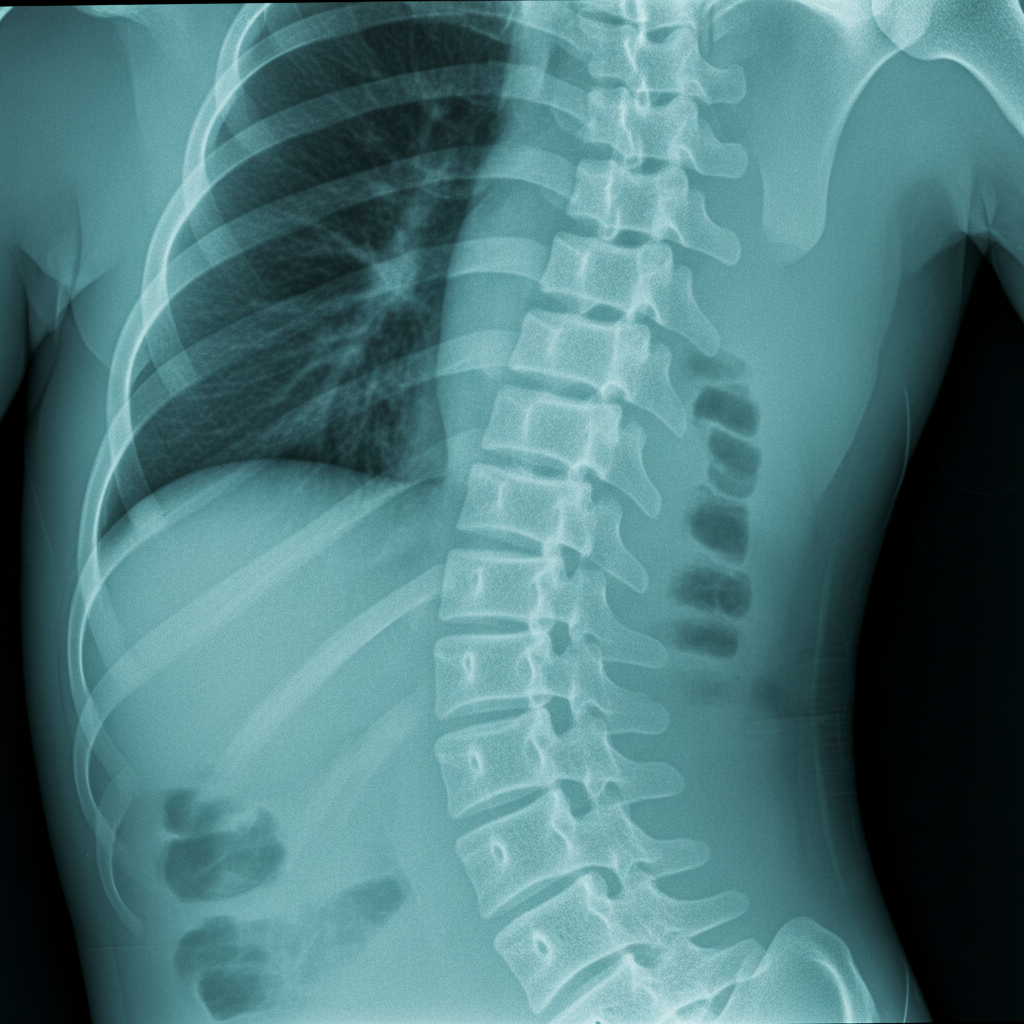

먼저, 흉추압박골절이 정확히 뭘 의미하는지부터 알아봐야겠죠? 쉽게 말해 흉추는 우리 등 쪽에 있는 척추뼈를 말하는데요, 갈비뼈가 연결된 부위부터 허리 위쪽까지를 포함해요. 이 뼈가 외부 충격이나 약해진 뼈의 힘을 이기지 못하고 주저앉거나 납작하게 찌그러지는 것을 '압박골절'이라고 부른답니다. 상상만 해도 아찔하죠? 보통 높은 곳에서 떨어지거나, 교통사고처럼 강한 충격을 받았을 때, 또는 골다공증처럼 뼈가 약해진 상태에서 가벼운 충격만으로도 발생할 수 있어요.

흉추압박골절 후유장해 AI image

Photo by Google Gemini AI

“흉추압박골절은 단순히 뼈가 부러지는 것 이상의 의미를 가집니다. 척추뼈의 형태가 변형되면 신경학적 증상은 물론, 전신적인 균형 문제까지 유발할 수 있기 때문이죠.”

처음에는 극심한 통증으로 시작해서, 시간이 지나면서 통증이 좀 가라앉는다고 해도 척추가 변형된 상태로 굳어지면 여러 가지 문제가 생겨요. 등을 구부리거나 허리를 펴는 게 힘들어지고, 심하면 키가 줄어들거나 허리가 굽는 증상도 나타날 수 있답니다. 이런 상태가 바로 흉추압박골절 후유장해로 이어질 수 있는 시작점이라고 볼 수 있어요.